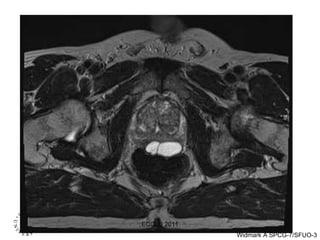

Prostate MRI  Cancer   (S Johansson) Axial Coronal ECCLU 2011